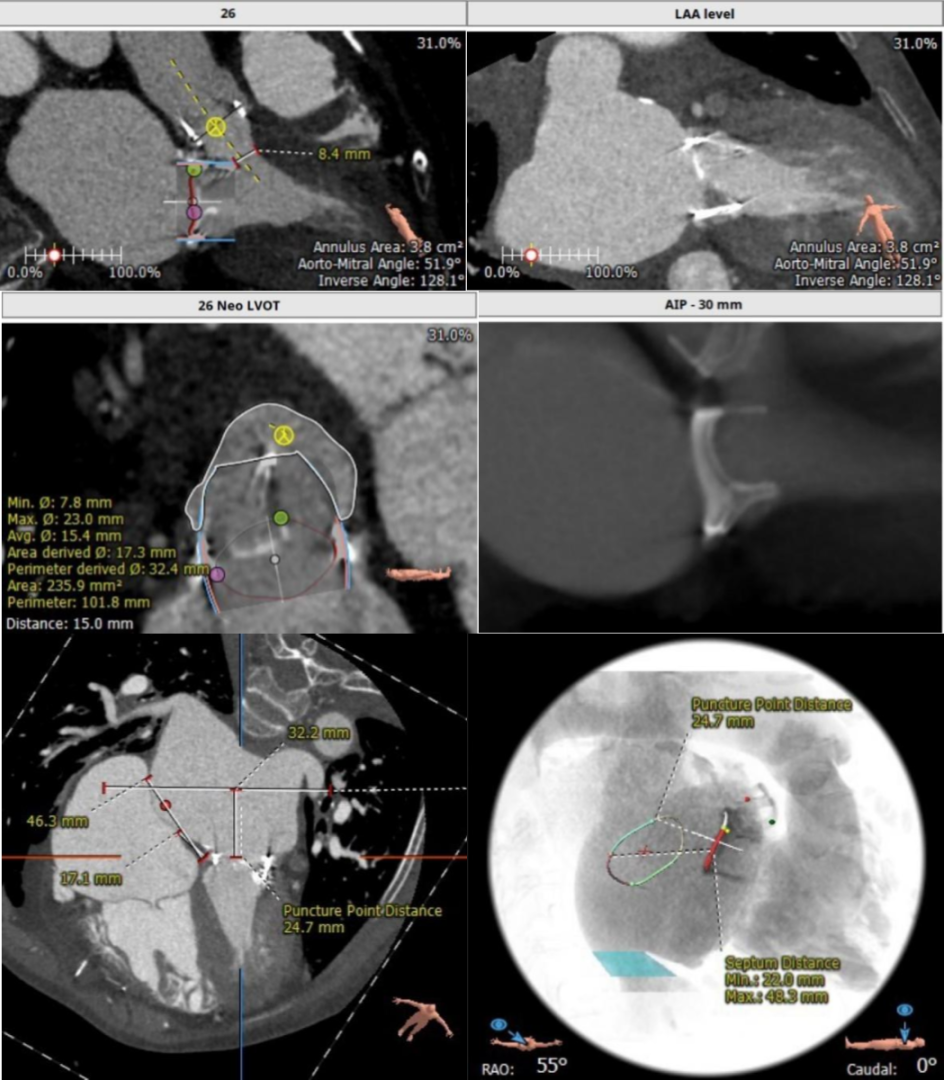

二尖瓣瓣中瓣CT评估